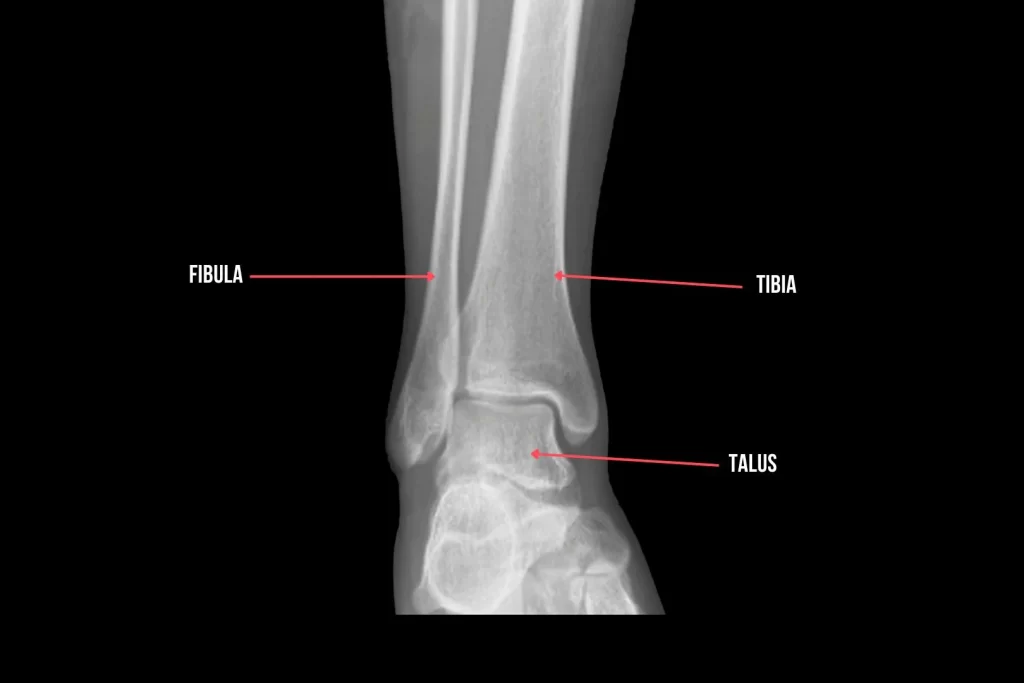

将您的踝关节想象成连接您的小腿和脚的桥梁。涉及的主要骨骼是胫骨(小腿骨)、腓骨(腓骨)和距骨(踝骨)。它们共同形成一个坚固的结构,使您可以轻松地行走、跑步和跳跃。它们是踝关节解剖的基础。